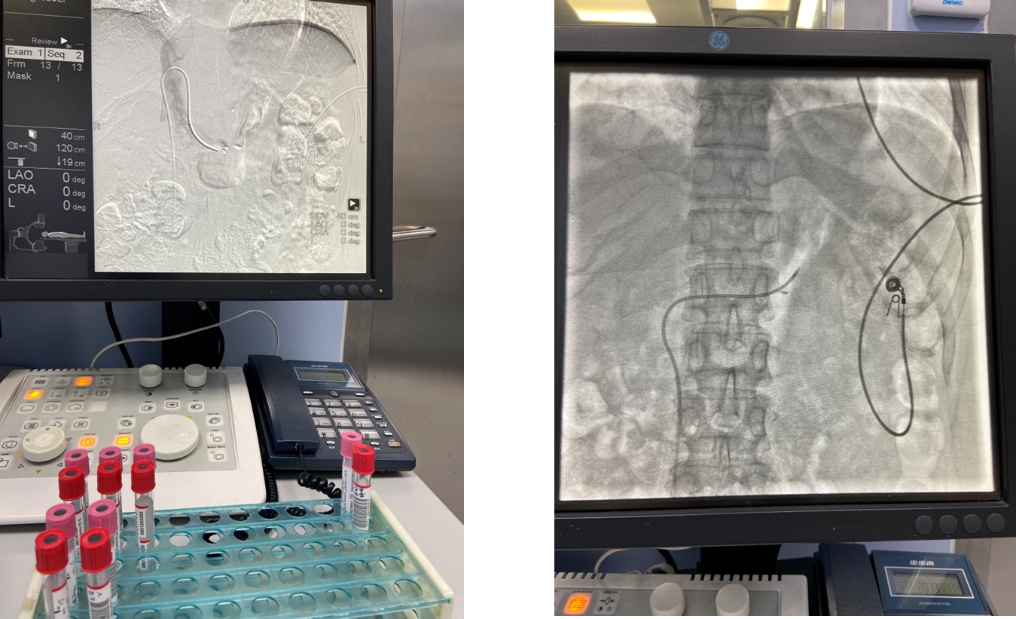

为了搞清楚这个问题,MDT团队的介入科徐霁充医师和内分泌代谢科合作,对刘女士进行了双侧肾上腺静脉采血(AVS),采用促皮质激素的持续静滴下的非同步双侧肾上腺静脉采血,检测激素分泌情况,终于明确刘女士的左侧腺瘤是功能侧,也就是说刘女士的高血压、低血钾是由左侧的肾上腺腺瘤引起的。